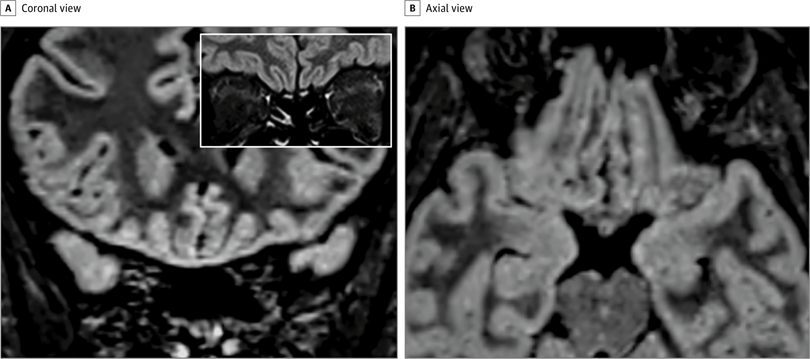

На 3-мерных и 2-мерных изображениях восстановления инверсии, ослабленных жидкостью, гиперинтенсивность коры была очевидна в правой извилине прямой мышцы ( Рисунок 1 ), а небольшая гиперинтенсивность присутствовала в обонятельных луковицах ( Рисунок 1 ). Потому что многие пациенты в Италии страдают аносмией.3, и изменение коркового сигнала свидетельствовало о вирусной инфекции, был проведен мазок, и анализ полимеразной цепной реакции с обратной транскрипцией дал положительные результаты для SARS-CoV-2. Во время контрольной МРТ, проведенной через 28 дней, изменение сигнала в коре полностью исчезло, а обонятельные луковицы стали тоньше и немного менее гиперинтенсивными ( рис. 2, 4 ). Пациент восстановился от аносмии. У 2 других пациентов с COVID-19 с аносмией, которым проводилась МРТ головного мозга через 12 и 25 дней с момента появления симптомов, аномалий головного мозга не наблюдалось.

Рис. 2. Последующее исследование магнитно-резонансной томографии у того же пациента через 28 дней от начала симптома.

Насколько нам известно, это первый отчет об участии мозга человека in vivo у пациента с COVID-19, показывающий изменение сигнала, совместимое с вирусной инвазией в мозг в кортикальной области (например, заднюю извилину прямой мышцы), которая связана с обонянием. Альтернативные диагнозы (например, эпилептический статус, изменения, подобные синдрому задней обратимой энцефалопатии, другие вирусные инфекции и анти- N- метил- d-аспартатный рецепторный энцефалит) маловероятны с учетом клинического контекста. Основываясь на результатах МРТ, включая незначительные изменения обонятельной луковицы, мы можем предположить, что SARS-CoV-2 может проникнуть в мозг через обонятельный путь и вызвать обонятельную дисфункцию нейросенсорного происхождения;

Для подтверждения этой гипотезы необходимы исследования спинномозговой жидкости и патологии. Наши и другие наблюдения за нормальной визуализацией головного мозга у других пациентов с обонятельной дисфункцией, связанной с COVID-19 4и исчезновение аномалий кортикальной МРТ при последующем исследовании этого пациента позволяют предположить, что изменения визуализации не всегда присутствуют при COVID-19 или могут быть ограничены очень ранней фазой инфекции. Кроме того, аносмия может быть преобладающим проявлением COVID-19, и это следует учитывать при выявлении и изоляции пациентов с инфекцией, чтобы избежать распространения болезни.